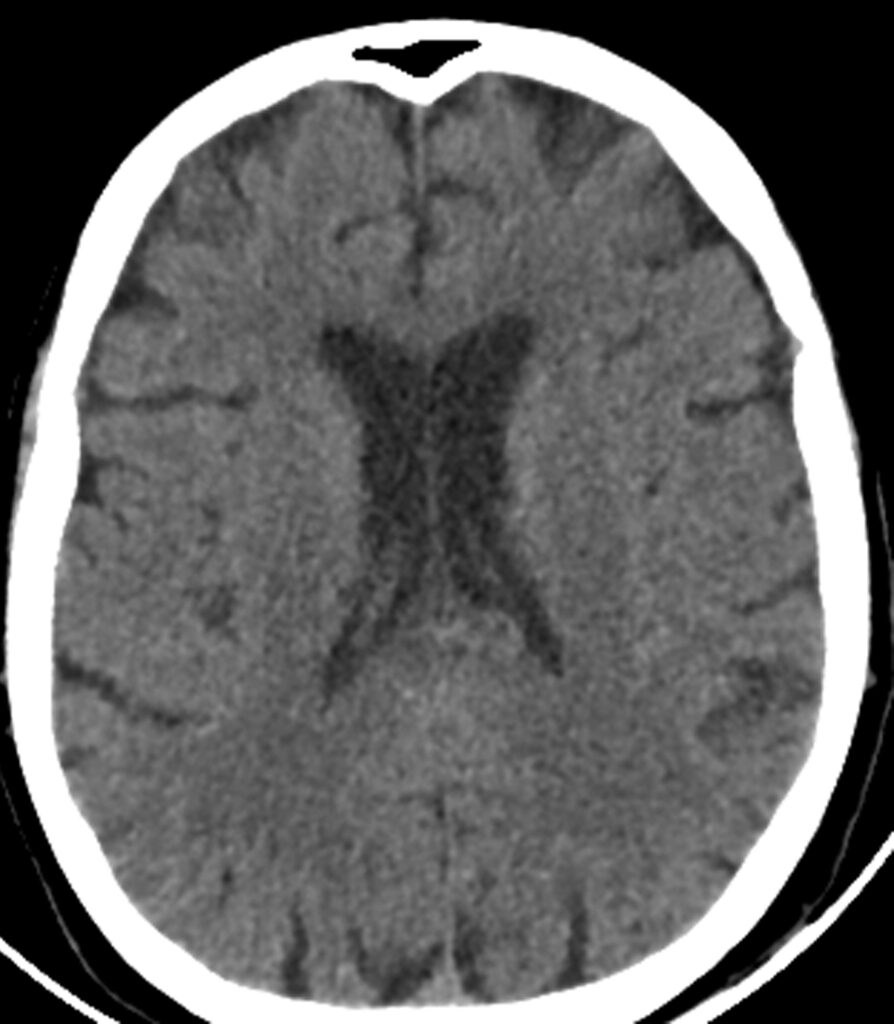

40-year-old woman with headaches, focal neurologic deficits

A 40-year-old woman with headaches and focal neurologic deficits including numbness and tingling in her hands and feet.